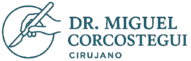

De manera general, lo que se conoce como una hernia es la salida de vísceras u otras estructuras intrabdominales a través de un orificio que se dilata excesivamente en la pared abdominal. En todas las personas, ese orificio ya existe de manera congénita y fisiológica en regiones características de la pared abdominal. Pero sus dimensiones deben ser milimétricas. Cuando por debilidad y laxitud de las estructuras de la pared abdominal, el orificio se dilata excesivamente, ello permite que el contenido visceral intrabdominal se escape a través de dicho orificio (anillo herniario), formando el bulto característico que se notan las personas herniadas.

De manera general, lo que se conoce como una hernia es la salida de vísceras u otras estructuras intrabdominales a través de un orificio que se dilata excesivamente en la pared abdominal. En todas las personas, ese orificio ya existe de manera congénita y fisiológica en regiones características de la pared abdominal. Pero sus dimensiones deben ser milimétricas. Cuando por debilidad y laxitud de las estructuras de la pared abdominal, el orificio se dilata excesivamente, ello permite que el contenido visceral intrabdominal se escape a través de dicho orificio (anillo herniario), formando el bulto característico que se notan las personas herniadas.

Al dilatarse excesivamente el anillo inguinal profundo, junto a esas estructuras anatómicas descritas, se intruce también la membrana peritoneal también llamado peritoneo, que se convierte en el llamado saco herniario formando lo que llamamos hernia inguinal.

Al dilatarse excesivamente el anillo inguinal profundo, junto a esas estructuras anatómicas descritas, se intruce también la membrana peritoneal también llamado peritoneo, que se convierte en el llamado saco herniario formando lo que llamamos hernia inguinal.